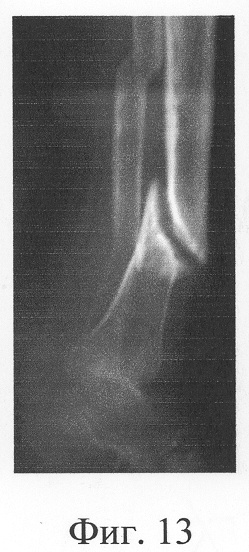

Больная П., 42 лет, поступила для оперативного лечения с диагнозом «атрофические ложные суставы обеих большеберцовых костей; сросшийся с укорочением 5 см перелом левой бедренной кости, хронический остеомиелит левой бедренной кости, фаза ремиссия; посттравматическая невропатия правого малоберцового нерва». В анамнезе – накостный, а затем дважды внеочаговый остеосинтез левой большеберцовой кости с исходом в ложный сустав; 4 операции внеочагового остеосинтеза правой большеберцовой кости, в том числе с костной пластикой; сроки фиксации в аппарате от 5 до 10 мес. Результат не достигнут: с обеих сторон сформировались ложные суставы (фиг.8-11 – клинические и фиг.12-15 – рентгенологические данные до лечения по предложенному методу).